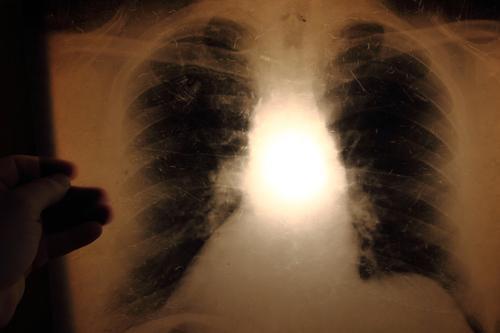

La tuberculose est une maladie contagieuse, secondaire à une infection au bacille de Koch (Mycobacterium tuberculosis). Cet agent bactérien est transmis par voie aérienne, en particulier lors de la toux. Chez environ 10 % des personnes infectées, elle n’est pas contrôlée par le système immunitaire, et des complications peuvent s’installer, notamment au niveau pulmonaire.

Une toux persistant plus de deux semaines, un amaigrissement important et une fièvre modérée mais persistante font partie des symptômes classiques. Les personnes atteintes doivent être mises à l’isolement pendant 10 à 20 jours, et sont traitées par des cocktails d’antibiotiques, pendant environ 6 mois.